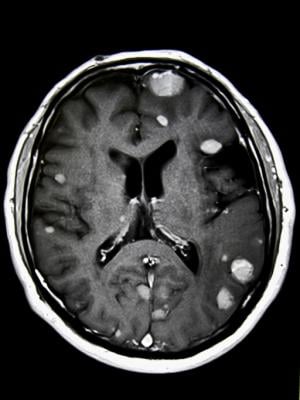

Brain metastases form when cancer cells spread to the brain from a primary tumor located elsewhere in the body, most commonly lung cancer, breast cancer or melanoma. Brain metastases are the most common type of brain tumors – roughly 10 times more common than primary brain tumors. They develop in 20-40% of people diagnosed with cancer, with approximately 200,000 new cases diagnosed in the U.S. each year.

Radiation therapy is commonly used to manage brain metastases, prolong survival and provide relief from headaches, dizziness and other neurological problems these tumors can cause. Whole-brain irradiation, however, is associated with cognitive deterioration. To reduce these adverse effects and preserve patients’ quality of life, researchers developed advanced radiation therapy techniques including stereotactic radiosurgery (SRS) and hippocampal avoidance whole brain radiation therapy (HA-WBRT) that result in fewer side effects. These treatments deliver therapeutic doses of radiation to the tumors while limiting exposure to healthy brain tissue.